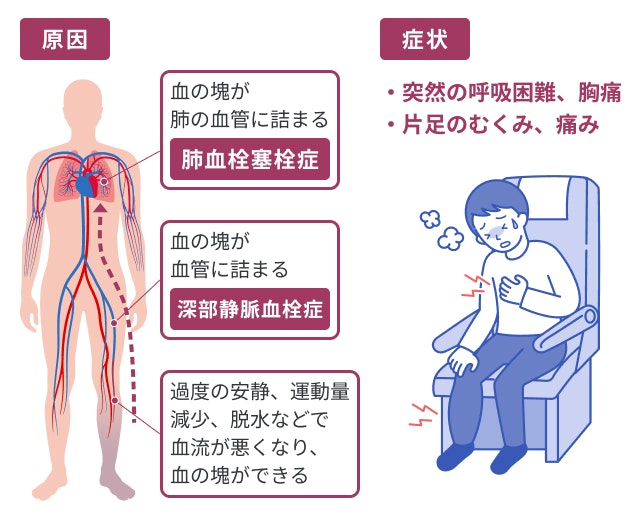

エコノミークラス症候群のイラスト素材29373435- PIXTA。

川崎 静脈血栓塞栓症浅田内科・循環器内エコノミークラス症候群。

エコノミークラス症候群広島の調剤薬局 FINE PLUS まえだ薬局・プラス薬局 のブログ。

4 エコノミークラス症候群 肺血栓塞栓症 に関するQ&A - 4 エコノミークラス症候群 肺血栓塞栓症 に関するQ&A -災害時の対応について一般社団法人日本呼吸器学会。

エコノミークラス症候群病気と治療の検索サイト「メディカルブレイン」。

肺血栓塞栓症・エコノミークラス症候群 男性 のイラスト – フリーイラスト素材集 KuKuKeKe。

エコノミークラス症候群震災時に起こりやすい健康問題と予防法 1看護roo! カンゴルー。

4 エコノミークラス症候群 肺血栓塞栓症 に関するQ&A - 4 エコノミークラス症候群 肺血栓塞栓症 に関するQ&A -災害時の対応について一般社団法人日本呼吸器学会。

エコノミークラス症候群 深部静脈血栓症 メカニズムのイラスト素材29374549- PIXTA。

静脈血栓塞栓症ではどのような症状がありますか? 静脈血栓塞栓症。

エコノミークラス症候群:入院中に死亡8件 医療事故調査毎日新聞。